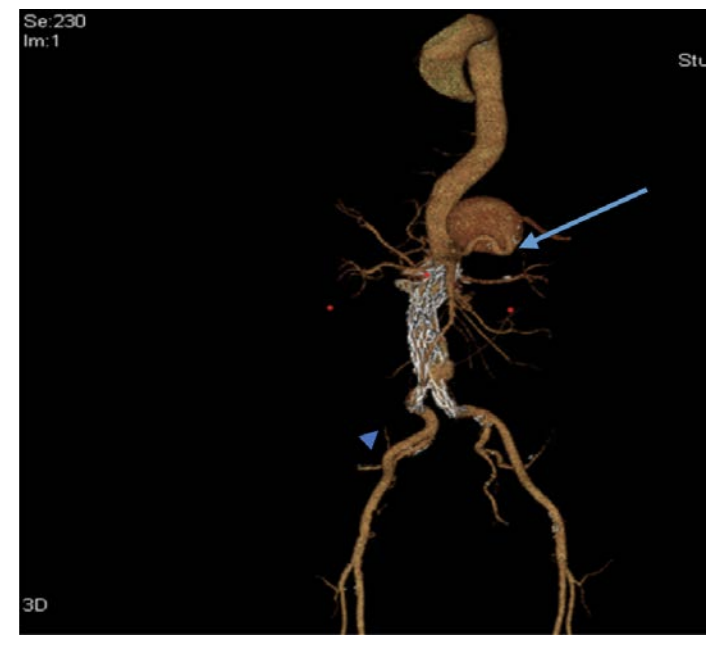

The patient was taken directly to surgery. An intraoperative aortogram revealed a nipple like projection at the distal part of the aorta and this was probably the area where he had ruptured (Figure 1). The patient underwent endoluminal graft placement under local anesthesia.

The postoperative course was uneventful. Since the patient did not get a preoperative CT scan, we decided to do a CT scan prior to his discharge. The CT scan revealed a left perinephric and retroperitoneal hematoma adjacent to prior AAA rupture and an incidental large 7 cm middle 1/3 splenic artery aneurysm (Figure 2), for which the patient underwent coil embolization of the splenic artery aneurysm. Postoperatively, the patient did very well and a repeat CT scan yielded no evidence of splenic infarction or other pathology.